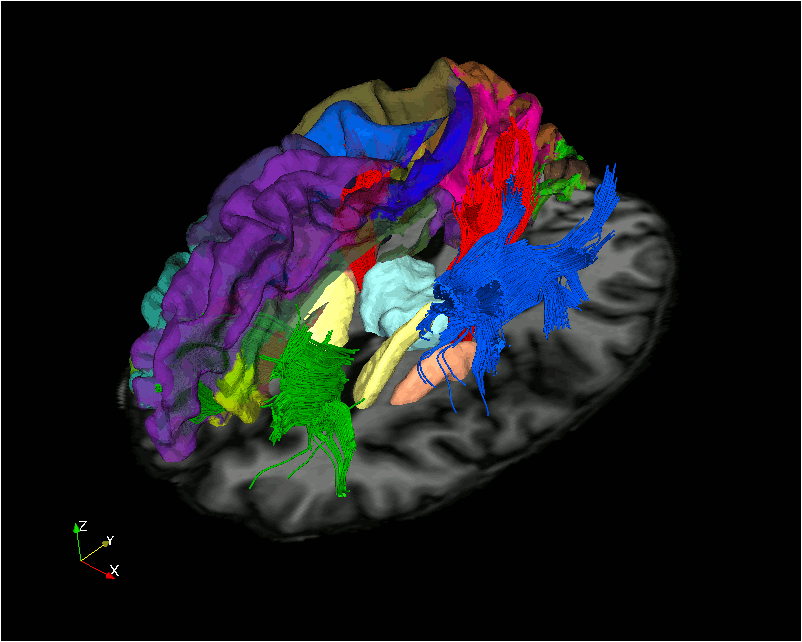

Analysis - Reconstruction

08-10 Tensor reconstruction

11-12 fODF reconstruction

13-14 Tractographies

FA

AD

RD...

CSD PEAKS

NUFO